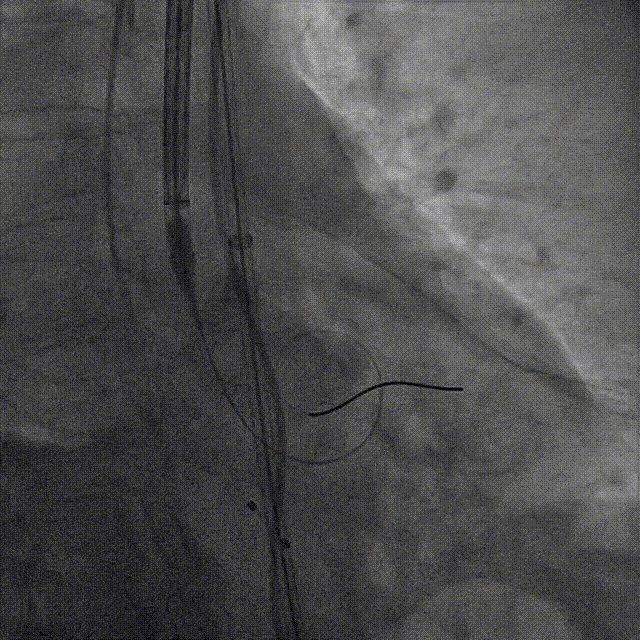

彭小平教授 南昌大学第一附属医院 不断探索医疗可能,筑牢患者长期保障 TAVR 治疗的终极目标,不仅是完成一次手术,更是为患者构建长期稳定的生命保障,而瓣膜耐久性是直接关乎患者后期是否需要二次手术的关键所在。全球首款预装干瓣的问世,为临床提供了全新的选择方案。厂家的15 年质保承诺,是源于材料研发的突破与临床验证的底气。从临床角度,如未来瓣膜可以耐久15年,则可大大减少患者反复就医的身心负担与经济压力,本质上是为患者的长期健康 “投保”。 人生的每一次选择,都需要慎重。相信在行业的前行中,我们不断探索医疗的可能性,让每一次治疗都能真正护航患者长远健康! 患者病史 主诉与现病史:3 年前开始出现胸闷、气促,活动后(如上楼、上坡)症状加重,休息后可缓解,当地医院心脏彩超提示主动脉瓣狭窄,未予特殊治疗;2 年前发现血压轻度升高,口服阿奇沙坦片(40mg,每日 1 次)降压,血压控制尚可;近 1 个月胸闷气促症状明显加重,2025 年 10 月 13 日外院心脏彩超提示主动脉瓣重度狭窄,为进一步诊治入院。 既往史:高血压病史 2 年,规律服用阿奇沙坦片(40mg qd);1 年余前因外伤致腰椎骨折,保守治疗后痊愈;有慢性阻塞性肺疾病病史;有胃窦糜烂、十二指肠球部溃疡史,2023 年曾发生急性上消化道出血;有真菌性食管炎、多发性结肠息肉病史。 术前超声提示:主动脉瓣钙化,主动脉瓣狭窄(重度),左室肥厚,升主动脉增宽。 二尖瓣反流(轻度),三尖瓣反流(轻度),肺动脉瓣高压(轻度)。 左室舒张功能减低,收缩功能正常,左室射血分数 74.7%。 术前CT:Type0型二叶瓣,瓣叶增厚并极重度钙化,钙化主要分布在瓣叶基底部,延伸到左室流出道。主动脉瓣环径24.8mm;升主动脉狭窄后扩张至主动脉弓,双侧瓣叶开口高度可,窦部空间可,STJ内径增宽,升主动脉内径可,预估冠脉低风险;主动脉水平夹角49.1°,非横位心;主动脉弓角、弓距可;“自杀左室”,建议术前补液,ECMO湿备,术中注意循环崩溃。 外周双侧入路内径可,髂总动脉有零星散状钙化,双侧股动脉均能通过20F大鞘,右股低分叉。 手术策略:推荐使用右侧股动脉为主入路,左侧股动脉为辅助入路;右股分叉上方1cm穿刺;推荐使用18mm球囊预扩,预装AV23瓣膜。 手术过程:在右股动脉穿刺建立通路后,顺利送入大鞘,经食道超声及血管造影确认路径稳定。18mm球囊预扩后评估冠脉灌注良好,后将Prostyle A® AV23瓣膜精准释放于目标位置,20mm球囊后扩,超声显示轻微瓣周漏,术后即刻造影显示无明显反流,峰值压差由术前的80mmHg降至12mmHg,心功能明显改善,患者生命体征平稳。 18球囊预扩无腰无漏 输送器跨瓣顺利 定位 平稳释放瓣膜 20球囊后扩 最终造影,位置良好,轻微瓣周漏 Prostyle A®预装干瓣——助力临床最优化解决方案 1、流入端桶状设计:流入端桶状的设计,锚定迅速,有效减少释放步骤,提升植入稳定性; 2、平衡的收腰设计:二叶瓣小心室患者对瓣膜径向支撑力提出更高要求,Prostyle A®均衡的收腰设计可更好适应小瓣环及不规则瓣口结构,保证了EOA,有效降低了循环崩溃风险,提高瓣膜的耐久性; 3、预装干瓣 便捷顺安:金仕生物专利抗钙化技术运用纳米技术去除组织内的细胞碎片和磷脂,封闭游离醛基,从根本上阻断了瓣膜钙化的多项因素,显著提升了瓣膜的耐久性;同时,相比较传统戊二醛保存方式,干式存储最大限度的保留心包的亲水亲油平衡,还原组织天然曲柔性,进一步保障了瓣叶开合,保证长期耐久性; 专家简介 彭小平 南昌大学第一附属医院(点击查看专家详细简历) · END ·